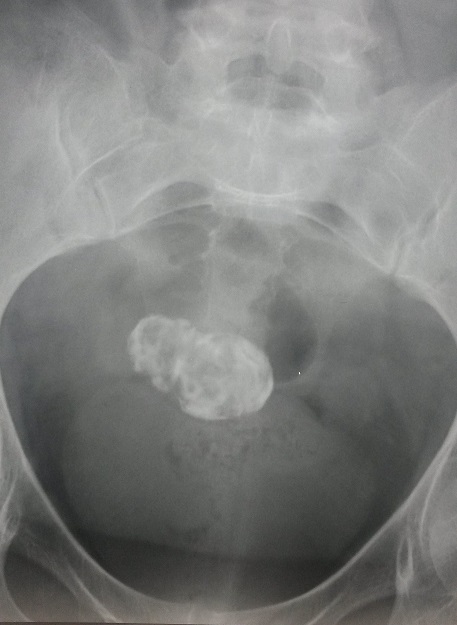

Figure 1: arbre urinaire sans préparation: opacité pelvienne de tonalité calcique hétérogène faisant 60x30mm (naziha.khammassi@rns.tn)

Les fibromes ou myomes utérins sont des tumeurs bénignes encapsulées, constituées de tissu musculaire utérin. Ce sont des lésions fréquentes retrouvées dans près de 20% des cas chez des femmes de plus de 35 ans. Plus rarement, une femme jeune peut développer un fibrome. Nous rapportons l'observation d'une patiente âgée de 54 ans, ménopausée depuis 6 ans, hospitalisée pour exploration d'une mononeuropathie multiple sensitivo-motrice axonale associée à une neuropathie végétative à type de diarrhée motrice. Au cours de son hospitalisation la patiente a présenté une hématurie macroscopique totale. L'examen cytobactériologique des urines a éliminé une infection urinaire. Un arbre urinaire sans préparation a objectivé une opacité pelvienne de tonalité calcique hétérogène faisant 60x30mm. L'échographie abdomino-pelvienne a permis d'écarter une lithiase ou une tumeur des voies urinaires. L'examen gynécologique spécialisé a conclu à un fibrome utérin calcifié. La conduite à tenir était l'abstention thérapeutique. Devant une calcification pelvienne les principales étiologies sont essentiellement représentées par les tératomes ovariens, les fibromes calcifiés, les tumeurs urinaires ou digestives, les calcifications épiploïques et exceptionnellement le lithopédion qui est une forme particulière et rare de grossesse extra-utérine d'évolution chronique.